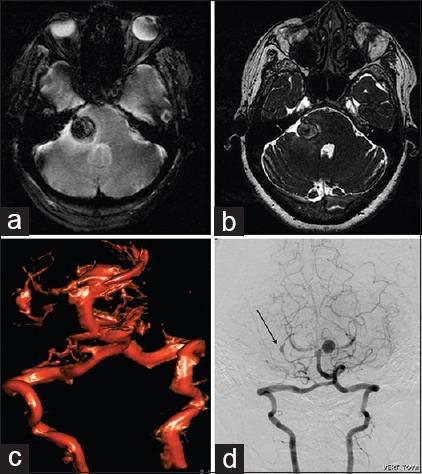

All patients with SCA were evaluated with computerized tomography angiography and/or digital subtraction angiography (DSA) prior to surgery. All patients in our series underwent microsurgical clipping and postoperative DSA to assess the extent of aneurysm occlusion. The Glasgow outcome scale (GOS) and the modified Rankin's scale (mRS) were used to grade their postoperative neurological status at discharge and 6 months, respectively.

Fourteen patients had SCA aneurysms (ruptured-9, unruptured-5). There were 10 females and 4 males with the mean age of 47.2 years (median - 46 years, range = 24-66 years). Subarachnoid hemorrhage (SAH) was seen in 11 patients. The mean duration of symptoms was 2.5 days (range = 1-7 days). The WFNS score at presentation was as follows: Grade 1 in 10 cases, II in 2 cases, III in 1 case and IV in 1 case. In the 9 cases with ruptured SCA aneurysm, average size of the ruptured aneurysms was 7.3 mm (range = 2.5-27 mm, median = 4.9 mm). The subtemporal approach was used in the first 7 cases. The extradural temporopolar (EDTP) approach was used in the last 5 cases. Complications include vasospasm (n = 6), third nerve palsy (n = 5) and hydrocephalus (n = 3). Two patients died following surgery. At mean follow-up 33.8 months (median - 25 months, range = 19-96 months), no patient had a rebleed. At discharge 9 (64%), had a GOS of 4 or 5 and 3 (21%) had a GOS of 3. At 6 months follow-up, 10/14 (71%) patients had mRS of 0-2, and 2 (14%) had mRS of 5.

14例患者患有SCA动脉瘤(破裂9例,未破裂5例)。有10名女性和4名男性,平均年龄为47.2岁(中位数 - 46岁,范围 = 24 - 66岁)。11例患者出现蛛网膜下腔出血(SAH)。症状的平均持续时间为2.5天(范围 = 1 - 7天)。就诊时的WFNS评分如下:1级10例,II级2例,III级1例,IV级1例。在9例破裂的SCA动脉瘤中,破裂动脉瘤的平均大小为7.3 mm(范围 = 2.5 - 27 mm,中位数 = 4.9 mm)。前7例采用颞下入路。后5例采用硬膜外颞极(EDTP)入路。并发症包括血管痉挛(n = 6)、动眼神经麻痹(n = 5)和脑积水(n = 3)。2例患者术后死亡。平均随访33.8个月(中位数 - 25个月,范围 = 19 - 96个月),无患者再次出血。出院时,9例(64%)患者的GOS为4或5,3例(21%)患者的GOS为3。在6个月随访时,14例患者中有10例(71%)的mRS为0 - 2,2例(14%)的mRS为5。